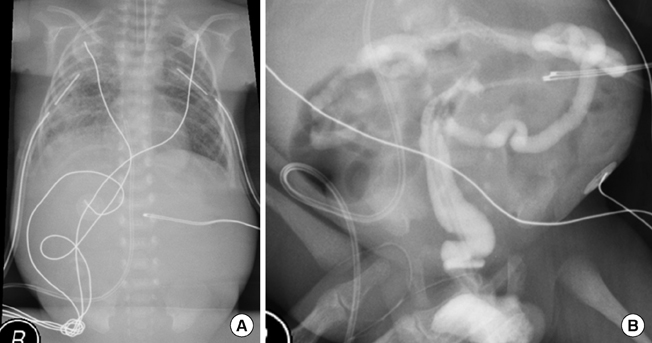

- Congenital myotonic dystrophy type 1 (DM1) presents severe generalized weakness, hypotonia, and respiratory compromise after delivery with high mortality and poor prognosis. We presented a congenital DM1 of premature twins in the 30th week of gestation. These twins were conceived by in vitro fertilization (IVF). Both babies presented apnea and hypotonia and had characteristic facial appearance. They were diagnosed DM1 by genetic method. They were complicated by chylothorax and expired at 100 and 215 days of age, respectively. Mother was diagnosed DM1 during the evaluation of babies. This is the first report on congenital DM1 which accompanied the chylothorax. More investigation on the association with chylothorax and congenital DM1 is recommended. With a case of severe neonatal hypotonia, congenital DM1 should be differentiated in any gestational age. Finally, since DM1 is a cause of infertility, we should consider DM1 in infertility clinic with detailed history and physical examination.

Figure